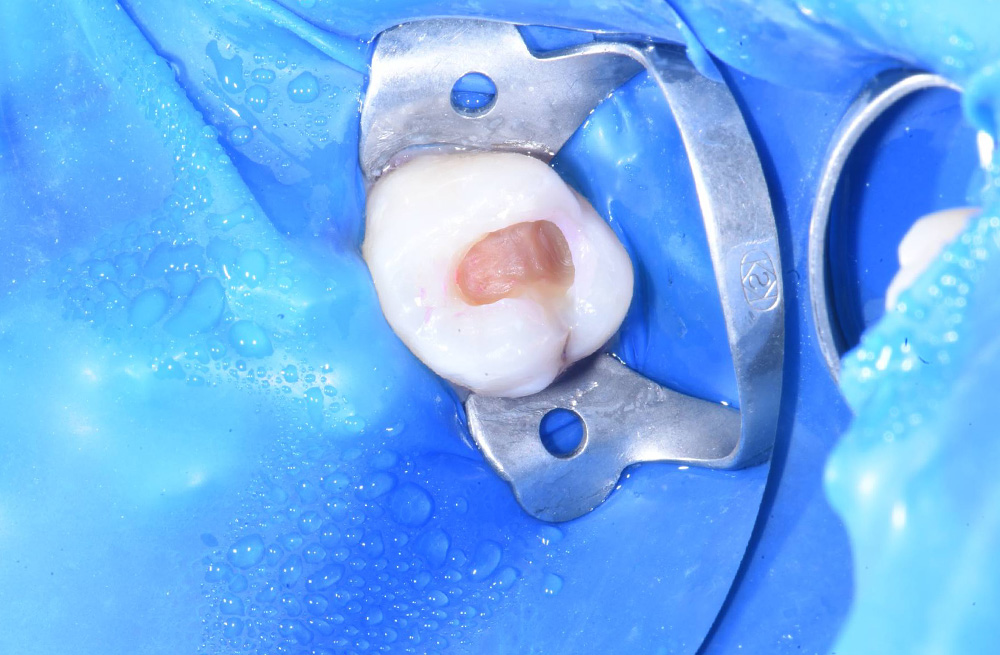

Лечение глубокого кариеса жевательных зубов под микроскопом с сохранением нерва и восстановлением контактного пункта